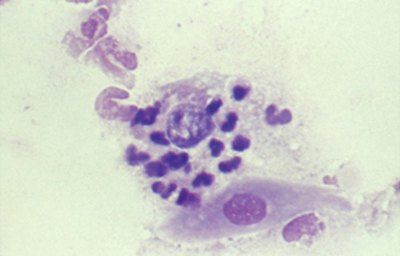

Tanto las Acanthamoebas vivas como sus productos de degradación son marcadamente antigénicos. En la respuesta celular a la infección por Acanthamoeba, los macrófagos las fagocitan (Fig 19) y los neutrófilos las destruyen vía secreción de mieloperoxidasas. (Figura 20) (Para no frenar la respuesta celular, preferimos no usar corticoides en el tratamiento de la infección activa). (El uso crónico de corticoides, en casos con superficie corneal alterada, es un factor primario en el desarrollo de una queratopatía cristalina infecciosa). La respuesta celular tiene como consecuencia, cuando la invasión por Acanthamoebas es estromal, que la abscesificación del estroma continuará aumentando a pesar del tratamiento, siendo su resolución lenta. (Figura 21, 22, 23, 24, 25, 26) (Figura, 27, 28, 29 y 30)

Fig. 20 Trofozoito rodeado por polimorfonucleares. Giemsa, Original x160